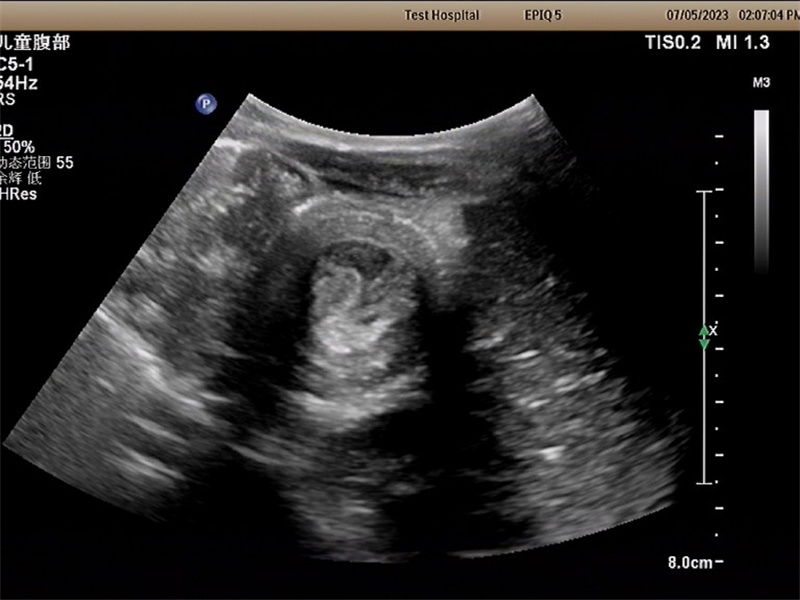

彩超检查是一种无创、安全、有效的检查方法,可以帮助医生准确诊断宝宝是否患有肠套叠。下面与家长分享肠套叠彩超检查的相关注意事项。

检查过程:彩超检查通常由专业的医生或技师进行。在检查过程中,医生会将一小部分凝胶涂抹在宝宝的腹部,然后用探头轻轻滑动在腹部上,以获取肠道的图像。这个过程通常不会给宝宝带来任何不适或疼痛。

安全性和效果:彩超检查是一种无创的检查方法,不会对宝宝的健康造成任何伤害。它可以提供清晰的图像,帮助医生准确诊断肠套叠,并及时采取必要的治疗措施。